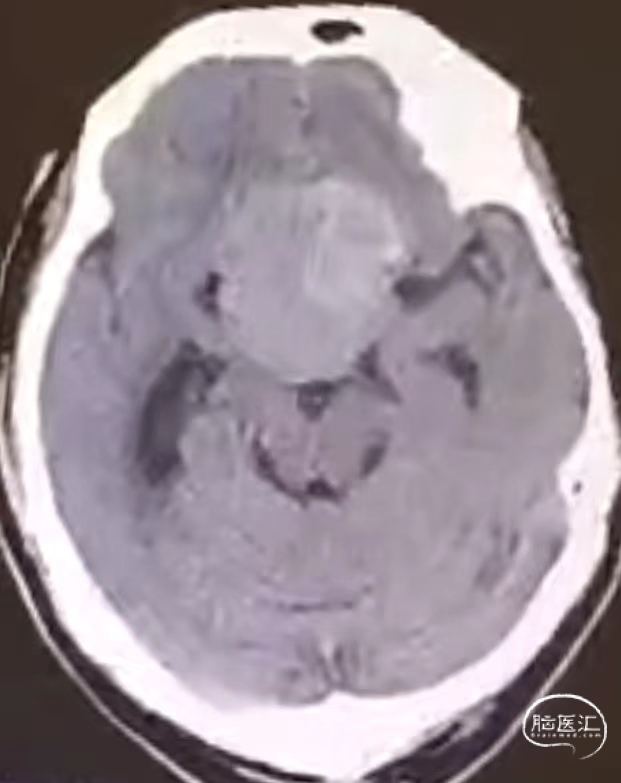

术前CT